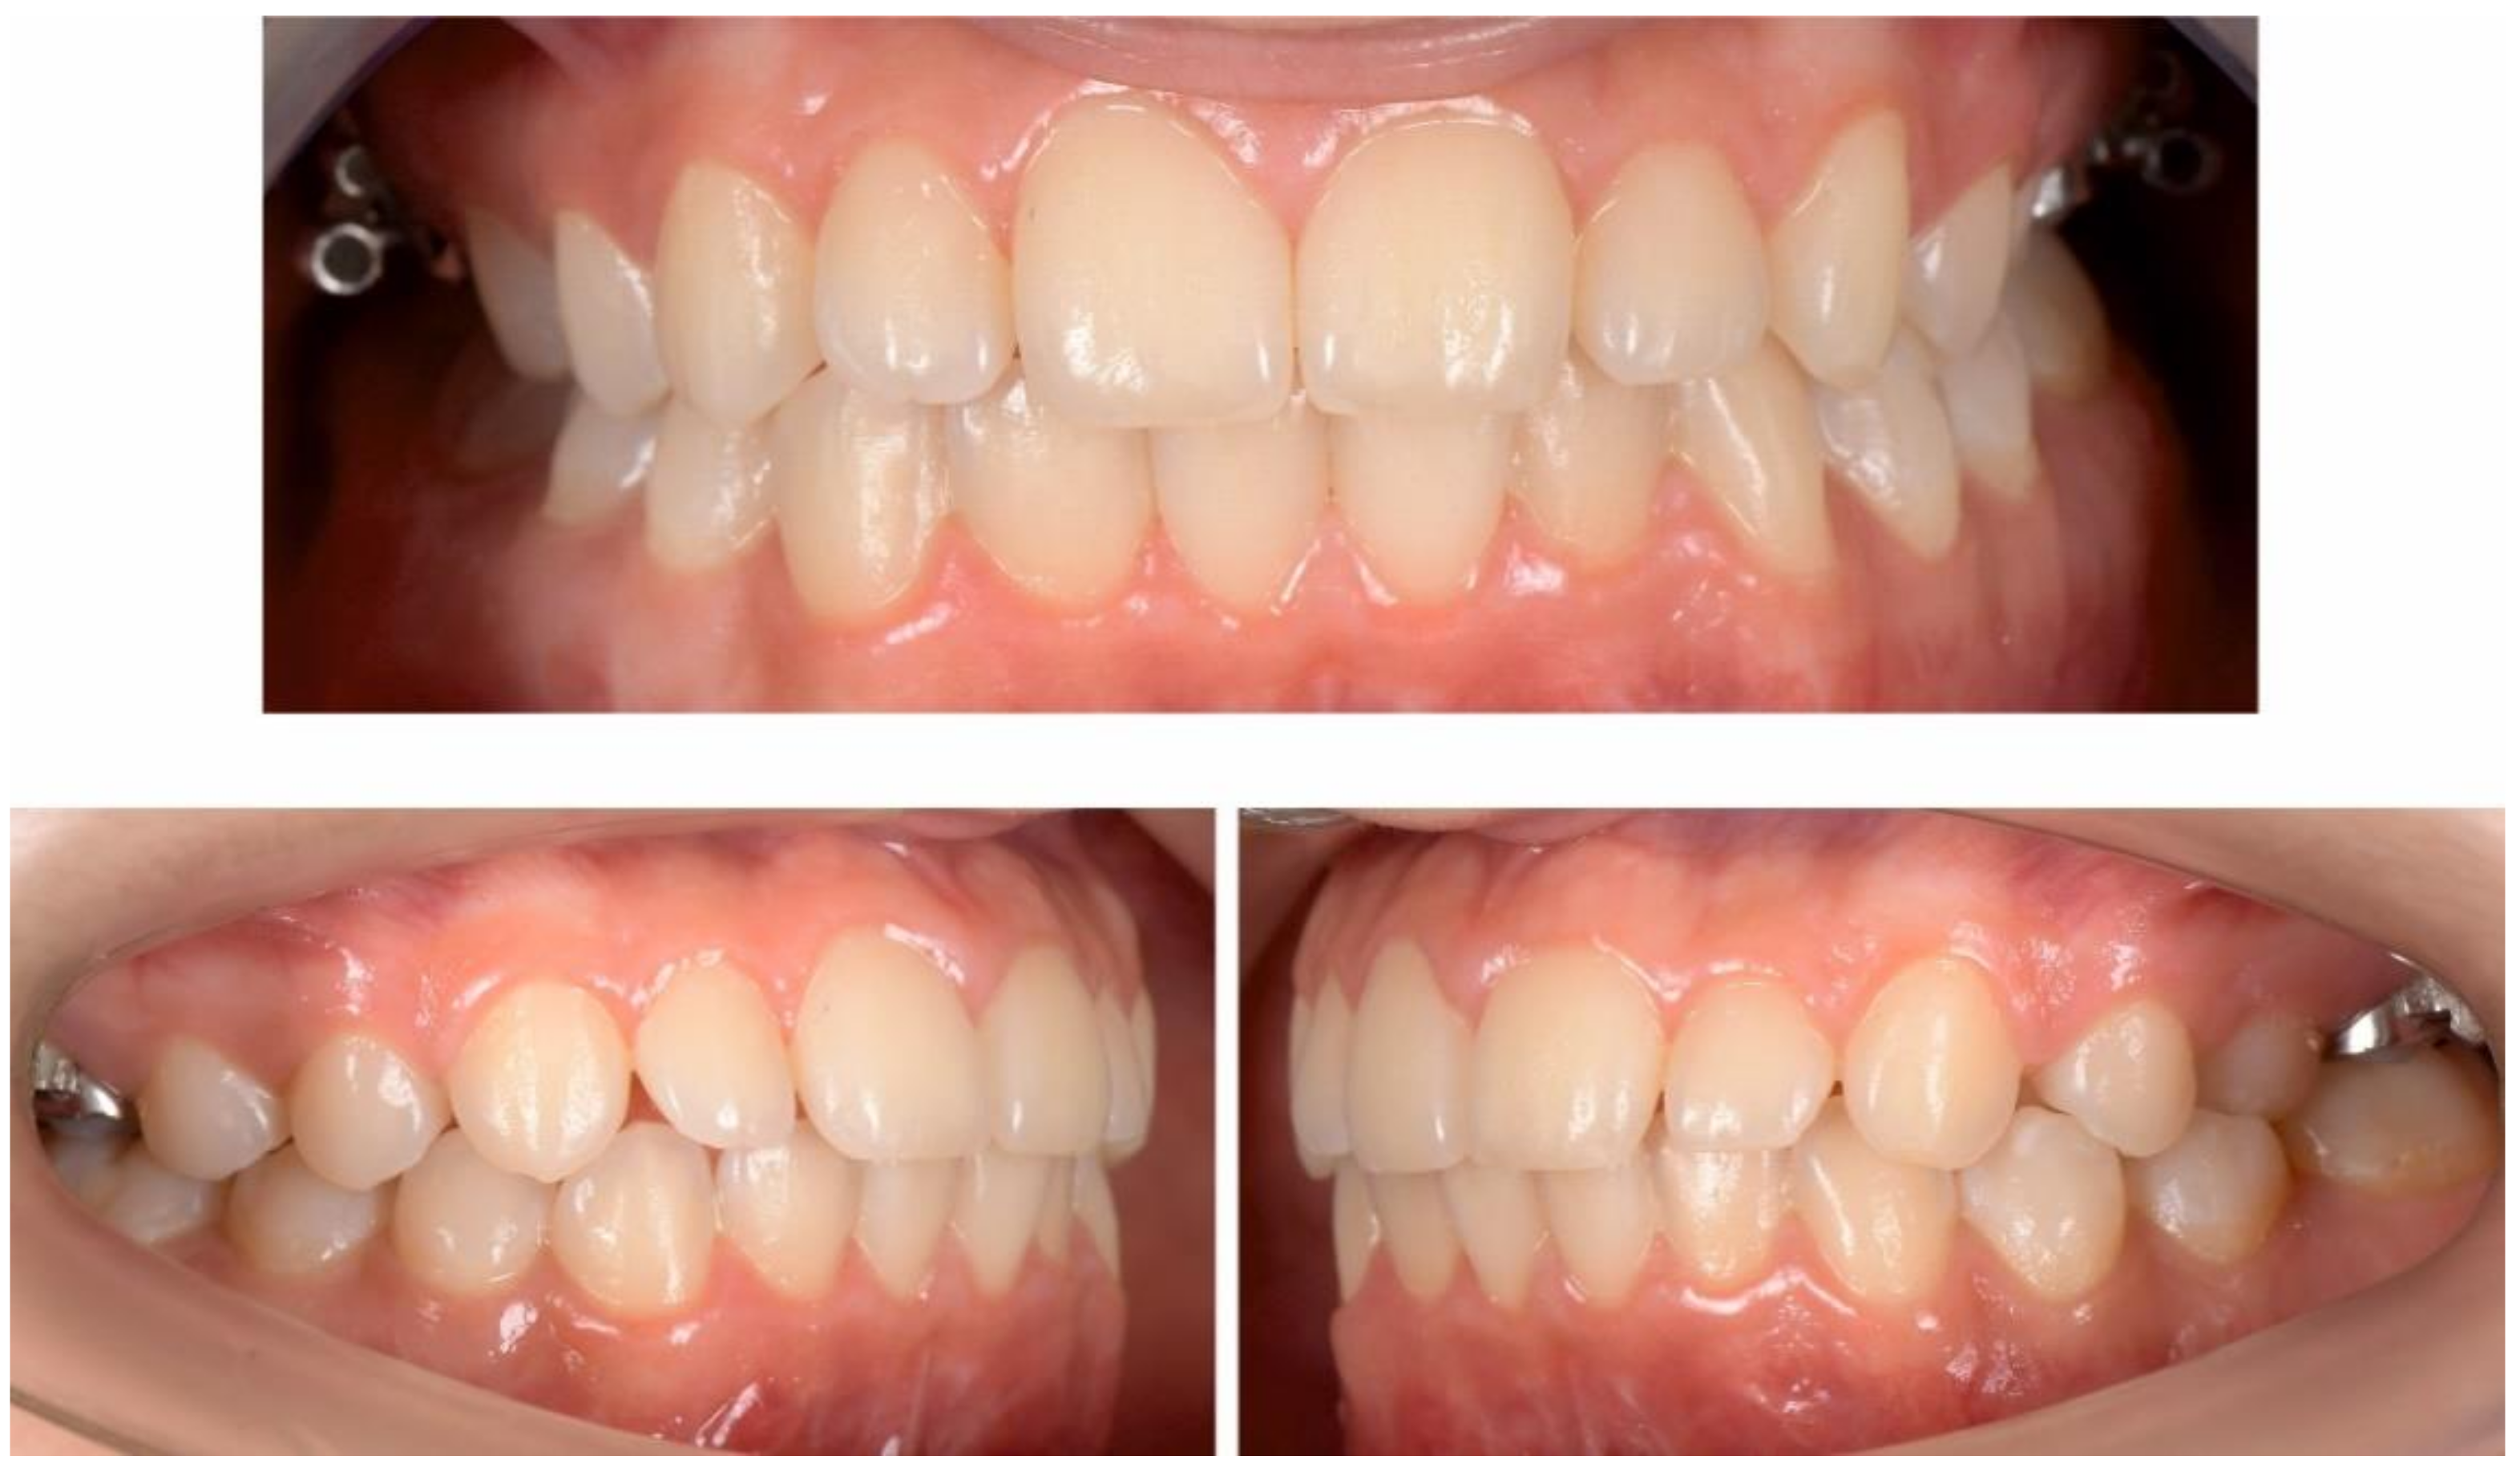

3. Results